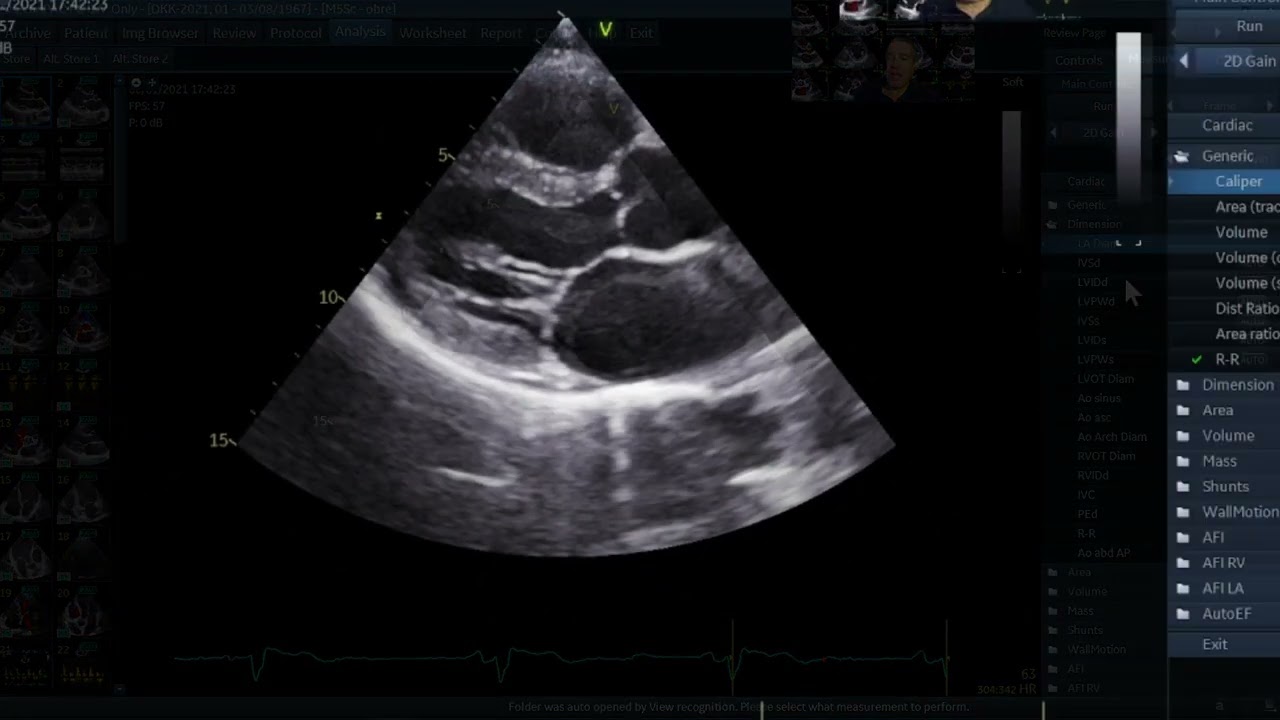

the paral long AIS view you can remember it by the 3 L's to success the personal long axis should have the left ventricle on the left side of the screen so for a visual here's what we're looking at for the personal long AIS view make sure the left ventricle is on the left of the screen before we go identifying what we see on the image it may be helpful to see a schematic representation on the ultrasound image toward the top of the screen we will see the right ventricle with the left ventricle beneath or deeper

to it and the interventricular septum in between in the left ventricle you can see the mitro valve and sometimes the papillary muscles to the right of the mitro valves you will see the left atrium in this image you can also see the aortic Valves and the aortic outflow track going back to the ultrasound image if we again imagine the heart as a cone the Apex is at the upper left of the screen with the base towards lower right anteriorly is at the top of the screen which makes sense because that is where you physically have

the Probe on the chest and deeper or towards the bottom of the image is the posterior portion of the heart the items to identify in the parasal Long exis View are the left ventricle the right ventricle the aortic valve and the mitro valve the left atrium the interventricular septum the descending aorta which will be important for distinguishing between a pericardial fusion and a plural Fusion we'll talk about that later the aortic outflow tract and the pericardium the parisal long AIS view is great for estimating e ection fraction there are a few studies that show that

eyeballing the ejection fraction by looking at the squeeze of the heart and how closely the anterior mitro valve leaflet gets to the interventricular septum is a good estimate of the gold standard Cardiology method of evaluating the EF additionally it is much faster and can easily be done in the emergency setting in this ultrasound image you can see that the anterior mitro valve leaflet is slapping up against the interventricular septum you can also see that there is good squeeze of the ventricle and that the ventricular walls are almost touching with each contraction this is indicative of

a normal ejection fraction of greater than 50% in this ultrasound image the anterior mitro valve leaflet does not quite make it to the inter ventricular septum Additionally the squeeze of the ventricles just isn't as good as the last image this EF is consistent with moderately depressed at 30 to 50% how do we know it is not severely depressed look at the next image in this image there's very little motion of the mitro valve leaflets and hardly any squeeze of the ventricles at all this is a sick heart with an ejection fraction of probably less than

30 if you want to quantitatively measure the ejection fraction and not exactly eyeball it you can do so using epss or E Point sepal separation this is a heart in the parasal long AIS view if we want to use epss we just throw down an M mode Spike at the tip of the anterior mitro valve leaflet you can freeze the image and this is what you will see the thicker white line represents the interventricular septum and the squiggly wavy lines beneath that represents the motion of the anterior mitro valve leaflet I don't know if you

noticed but the anterior mitro valve leaflet slaps twice on the interventricular septum in A Normal Heart the E represents the passive filling of the ventricles and a represents the atrial contraction the distance between the IVs and the squiggly lines show just how close the anterior mitro valve leaflet gets to the interventricular septum a distance of less than 7 mm is considered normal and greater than 10 is considered LV dysfunction or reduced EF 7 to 10 is sort of a gray area and needs to be taken into context notice this distance is greater than 10 mm